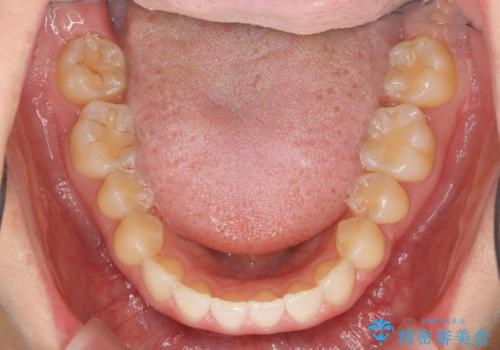

出っ歯に見える前歯の改善 部分ワイヤーとマウスピース矯正

- 出っ歯に見える前歯の改善を希望され、来院されました。

マウスピースでは改善の難しい歯の動きを部分ワイヤー矯正で整えたのち、奥歯の噛み合わせや細かい歯の並びをマウスピース矯正インビザラインで整えていきます。

最終的な前歯の並びに大変満足いただくことができました。